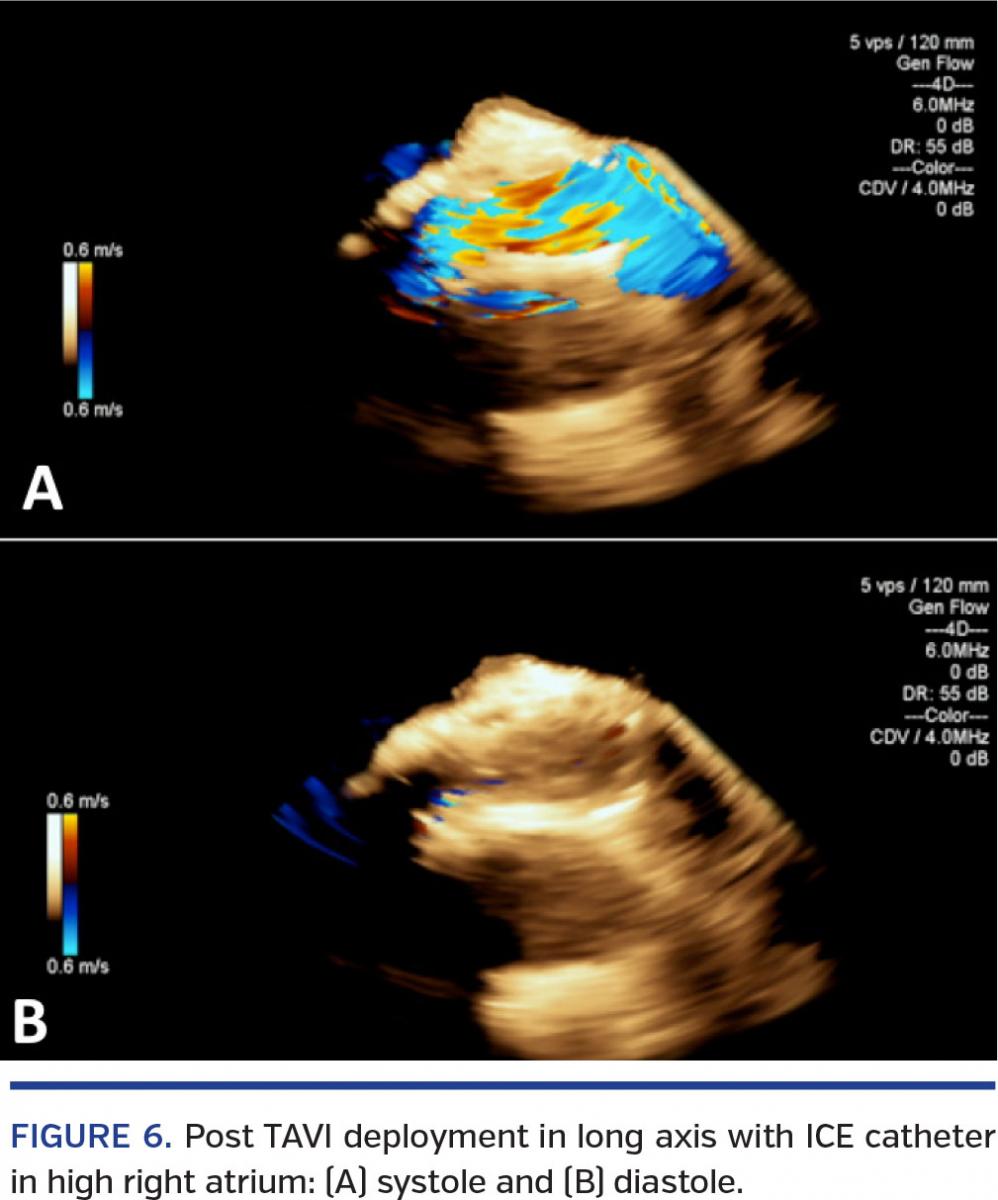

3D-ICE for TAVI (Figures 1-11)

Appropriate positioning of the TAVI device to the NCC annulus is of extreme importance and may be performed with great precision with either the Sapien or the CoreValve device. Since the deployment of the self-expanding Core-Valve is slower, continued attention to maintaining the position at the annulus without excessive need for angiographic contrast cannot be overemphasized. Appropriate assessment of the valve after deployment is crucial to assess transvalvular and paravalvular regurgitation. Such an assessment may be made in RT with the catheter in the cavoatrial junctions and the right ventricle. Coaptation of the leaflets in 3D views is also easily assessed.